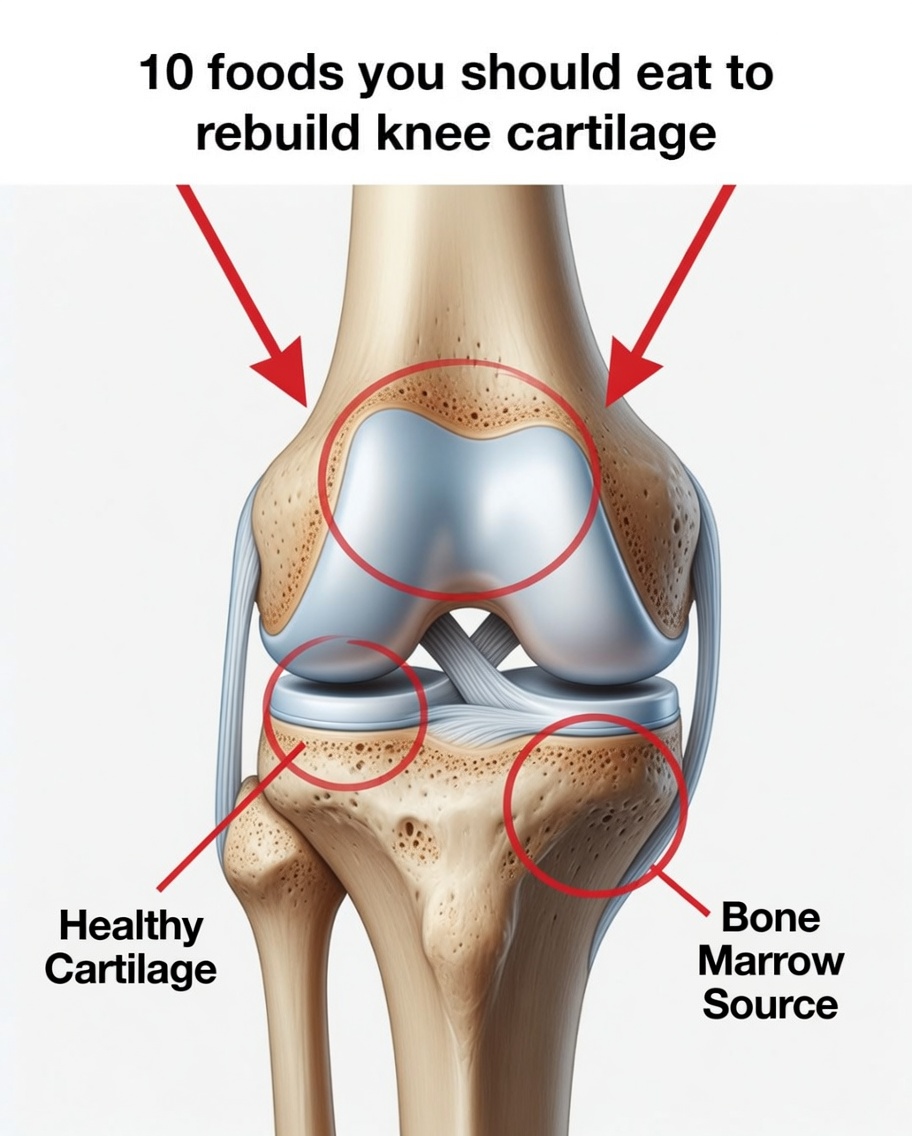

Grandma’s Natural Method for Cartilage Regeneration and Joint Support

Cartilage is essential for smooth, flexible movement because it cushions your joints and helps them glide without friction. Over the years, daily wear, aging, or injuries can weaken cartilage, leading to stiffness, discomfort, and reduced mobility. While medical treatments can help, many people also look to traditional, natural joint remedies passed down through generations.

1. Bone Broth for Collagen and Minerals

Bone broth was considered the go-to tonic for joints. It naturally contains collagen, amino acids, and minerals that support connective tissue and may help improve joint comfort and flexibility over time.

2. Gelatin-Rich Foods to Support Cartilage Structure

Because gelatin is derived from collagen, it has long been used in traditional diets to help with joint lubrication and cartilage support.